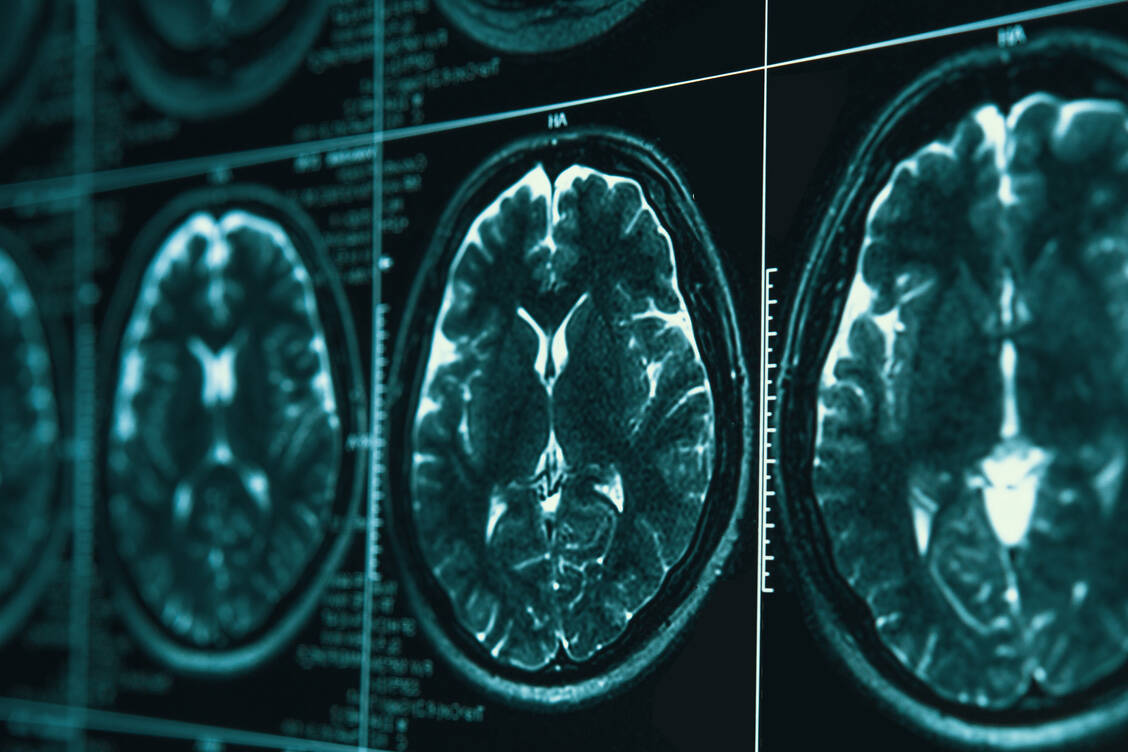

Tauopathien, zu denen auch die Alzheimer-Krankheit gehört, sind durch eine intrazelluläre Anhäufung und Aggregation von Tau-Protein gekennzeichnet. Die Bildung dieser pathologischen Aggregate könnte durch die Hemmung der Enzyme der Carboanhydrase-Familie reduziert werden, wie ein neuer Forschungsartikel nahelegt.

Tauopathien sind Krankheiten, bei denen die Pathologie vor allem durch Tau-Ablagerungen im Gehirn verursacht wird. Gibt es bereits zugelassene Wirkstoffe, die für die Behandlung dieser Erkrankungen infrage kommen? Dieser Frage ist ein Team um Dr. Ana Lopez und Farah H. Siddiqi vom Department of Medical Genetics der University of Cambridge in einer umfangreichen Repurposing-Studie nachgegangen. Die Forschenden testeten mehr als 1400 zugelassene Wirkstoffe und publizierten die Ergebnisse im Fachjournal »Nature Chemical Biology«.

Es zeigte sich, dass Carboanhydrase-(CA-)Hemmer Tau-Ablagerungen reduzieren und somit die Tau-Toxizität abmildern können. Durch die Hemmung der CA ändert sich der pH-Wert in den sekretorischen Vesikeln, wodurch phosphorylierte Tau-Proteine besser aus den neuronalen Zellen ausgeschleust werden.